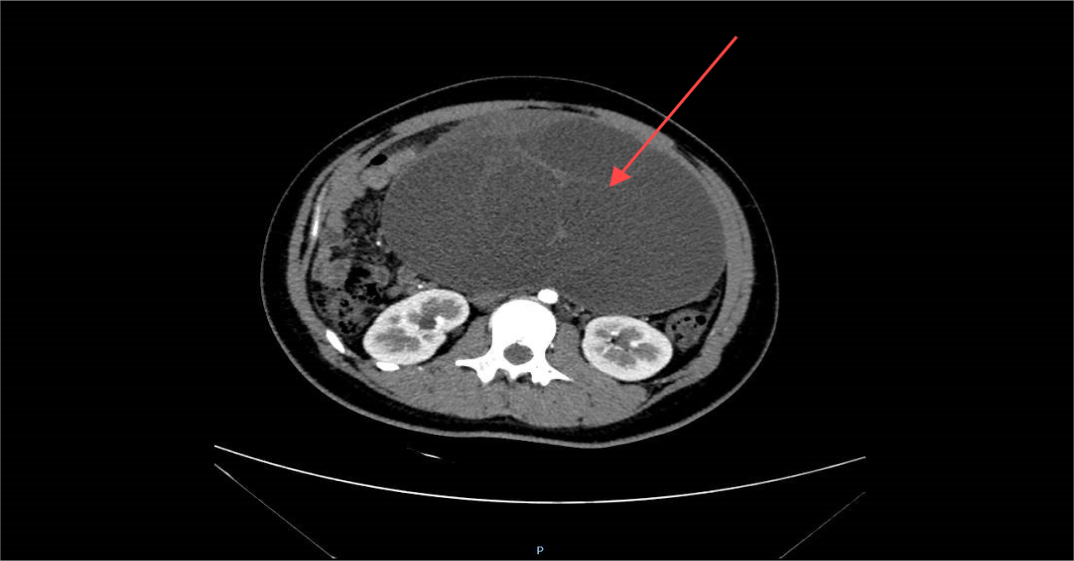

盆腹腔肿物的CT影像